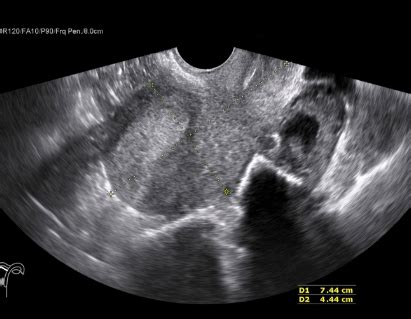

This is the most common type, where the transducer is placed on the surface of the skin. A gel is usually applied to improve contact and eliminate air pockets, ensuring better sound wave transmission. Traditional ultrasound scanners are used for a wide variety of applications, from abdominal scans to musculoskeletal imaging. This method is non-invasive and provides real-time images, allowing doctors to assess the structure and function of internal organs, blood vessels, and soft tissues.